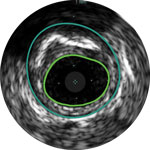

Behandlungsplan Beispiel 2

Lumen mit frischem Thrombus

Mikrokalzifizierung

Kalzifizierte Plaque mit Schallschatten

Gefässgrösse: 6 mm Durchmesser Plaquemorphologie: gemischte, thrombotische Plaque mit mittlerem Calcium Plaquegeometrie: exzentrische Läsion Position des Führungsdrahtes: wahres Lumen

Quick-Cross-Katheter: souverän komplexe Morphologien durchqueren Turbo-Power-Laser-Atherektomie: vorwärts gerichtetes, direktionales Abtragen zur Beseitigung von Thromben; Rotation für verbessertes Abtragen in kalzifizierten Läsionen AngioSculpt Scoring-Ballonkatheter: sicheres Aufweiten von Reststenosen4 Stellarex DCB: entwickelt für hohe Leistungsfähigkeit bei Kalfizifierungen